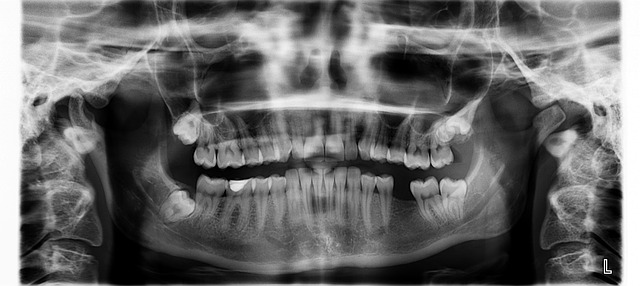

사랑니는 입안의 양쪽 끝 위아래에 하나씩 총 4개로 위치에 따라서 전부다 발치하거나 일부만 발치하게 됩니다. 사랑니의 위치가 잘 자리 잡은 경우 발치하지 않아도 상관없지만 통증이 느껴지거나 사랑니를 제대로 양치하지 않는 경우에는

사랑니에 충치가 생겨 다른 치아에도 충치를 유발할 수 있기 때문에 발치하는 것이 좋습니다.

사랑니는 보통 18세 이후에 많이 자라며 성인이 되고 난 뒤에도 사랑니가 자라지 않은 경우에는 매복 사랑니 일수 있습니다. 매복 사랑니인 경우 발치가 어려운 경우가 종종 있으며 사랑니의 위치가 안 좋은 경우에는 꼭 사랑니 발치를 잘하는 치과나 치과병원을 가는 것을 추천드리겠습니다.